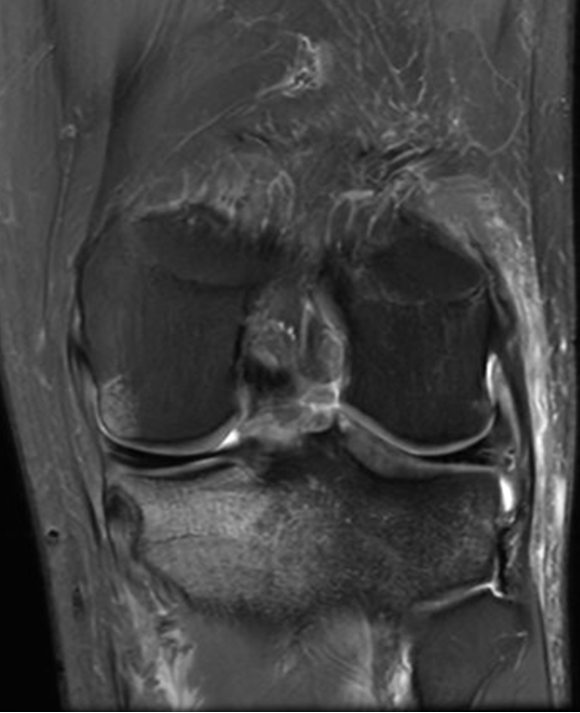

Q. De acuerdo con la imagen, qué signo radiológico identificas y en qué consiste.

Signo del ligamento colateral coronal. Consiste en la pérdida de la disposición oblicua del ligamento, observándolo completo en el un plano coronal, se observa en casos de inestabilidad estática de la rodilla comúnmente secundario a rotura del LCA.